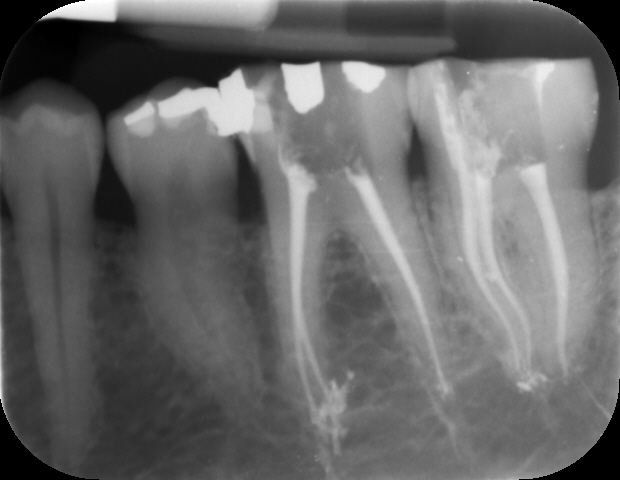

Negli ultimi anni la Radiologia Digitale sta sostituendo integralmente la Radiologia tradizionale.Il più moderno sistema digitale di acquisizione dati consente di visualizzare direttamente l’immagine radiografica sul monitor di un computer, ottimizzando, a beneficio del paziente, l’operato dell’ odontoatra. Il nostro studio utilizza la radiologia digitale da oltre 20 anni con piena soddisfazione nostra e dei nostri pazienti.